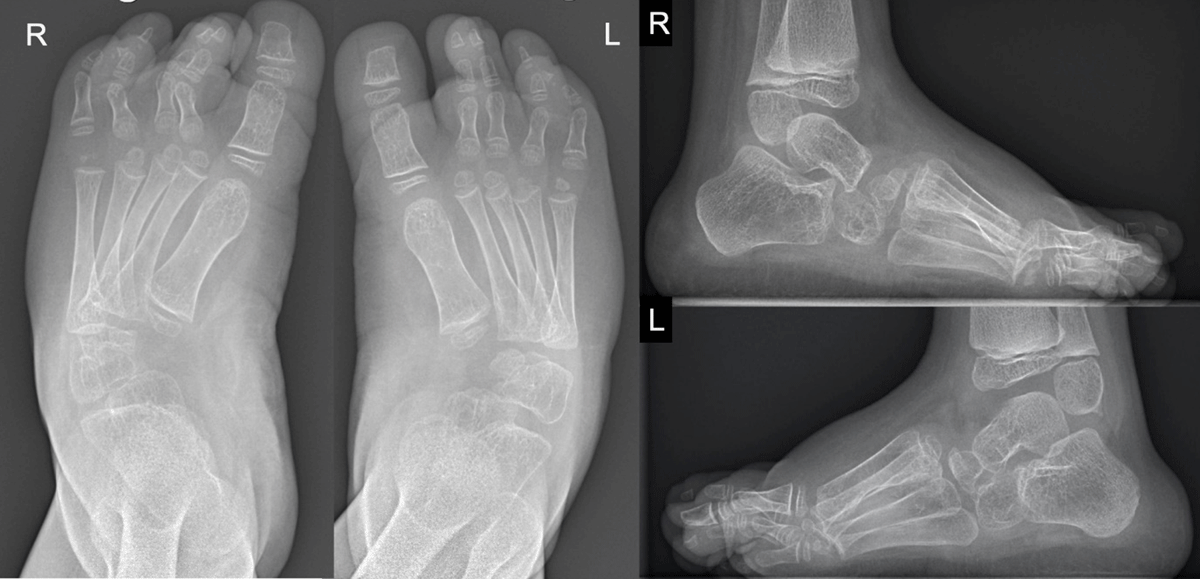

Figure 1

The radiographs of the ankle and feet reveal an extensive osteolysis of the tarsal bone, especially at the medial side of the midfoot and proximal metatarsal bone, causing a slight inward deformity of the forefeet.